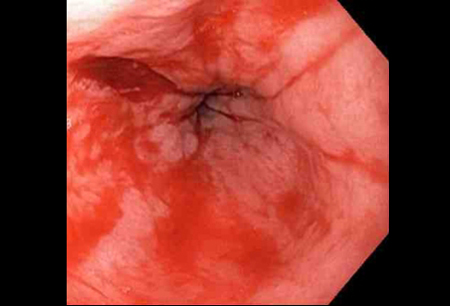

a laceração com sangramento ativo aparece como um defeito longitudinal vermelho com mucosa circundante normal

Do acervo de Juan Carlos Munoz, MD, University of Florida